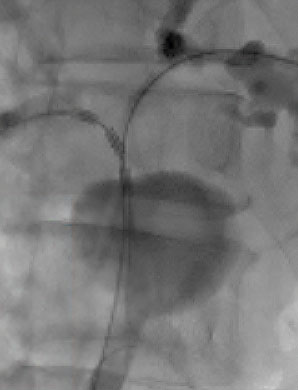

Fluoroscopic images demonstrate the use of ELRA™ in both the right and left hepatic ducts. These cases highlight the catheter’s ability to navigate complex ductal anatomies and deliver targeted ablation with precision. By restoring duct patency in strictures, ELRA™ provides a minimally invasive option that relieves obstruction and improves quality of life for patients.